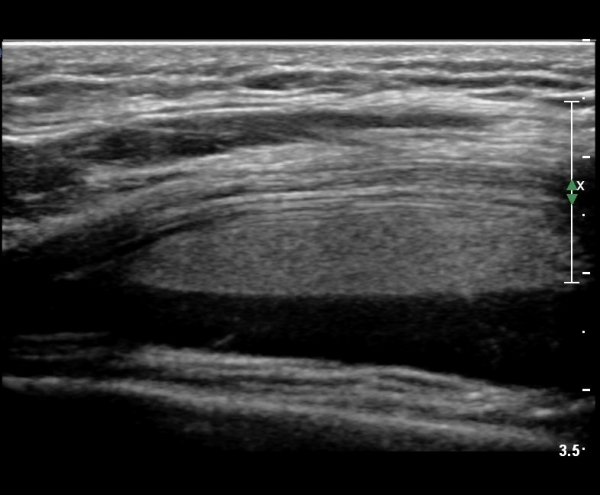

ÃÊÀ½ÆÄ °Ë»ç

¹«¸­ ÃøºÎ Á¾´Ü¸é°Ë»ç¿¡¼­ °í¿¡ÄÚ ¼ö¾×Àý·ù°¡ °üÂûµÊ( »çÁø 1).

¹«¸­ Àü¸éºÎ Á¾´Ü¸é°Ë»ç¿¡¼­ °üÀý³» ¼ö¾×Àú·ù°¡ °üÂûµÇ´Âµ¥ ¼ö¾×Àú·ù Ç¥Ãþ¿¡ °í¿¡ÄÚ Áö¹æÃþÀÌ °üÂûµÊ(»çÁø 2, 3)

¹«¸­ Àü¸éºÎ Ⱦ´Ü¸é°Ë»ç¿¡¼­ °üÀý³» ¼ö¾×Àú·ù°¡ °üÂûµÇ´Âµ¥ ¼ö¾×Àú·ù Ç¥Ãþ¿¡ °í¿¡ÄÚ Áö¹æÃþÀÌ °üÂûµÊ(»çÁø 4, 5)